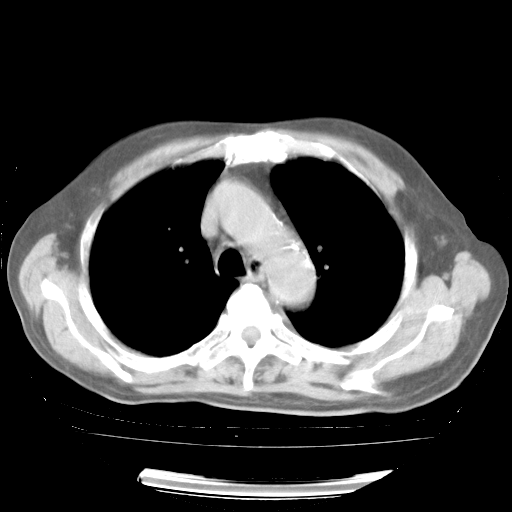

4月28日肺部CT——再次出现类似去年5月9日——磨玻璃样、间有“粟粒样”改变。

4月28日肺部CT